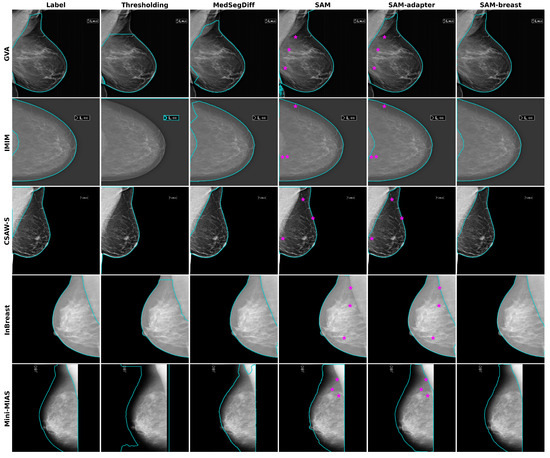

- GVA (proprietary): A multi-center dataset that covers 11 medical centers of the Generalitat Valenciana (GVA) as part of the Spanish breast cancer screening network. It includes 1785 women with ages from 45 to 70. The CC and MLO views were available for 10 out of 11 of the centers, while one center only collected the CC view. This dataset was used for training, validation, and testing. The dataset was randomly partitioned into 75% (2492 mammograms) for training and validation (10%) and 25% for testing (844 mammograms). All the mammograms are of the type “for presentation”. Further details about this dataset can be found in our previous work [9].

- IMIM (proprietary): A dataset composed of 881 images obtained at the Hospital del Mar Research Institute (IMIM). It was included solely for testing purposes to better evaluate the generalization performance of the models. This dataset consists of images from three different acquisition devices. One of these devices (Hologic Lorad Selenia, Marlborough, MA, USA) is older and was used to obtain images back in 2012. As a result, the image quality is lower, making the segmentation task more challenging. Only CC views were provided for this dataset, and they are also of the type “for presentation”.

- CSAW-S (public): The CSAW-S dataset, released by Matsoukas et al. [19], is a companion subset of CSAW [20]. This subset contains mammograms with expert radiologist labels for cancer and complementary labels of breast anatomy made by non-experts. The anonymized dataset contains mammograms from 150 cases of breast cancer, some of them including both MLO and CC views. We generated the breast masks for our experiments by combining the provided mammary gland and pectoral muscle labels, thus obtaining a total of 270 images with breast mask segmentations.

- InBreast (public): A well-known publicly available dataset [21]. It has ground truth annotations for the pectoral muscle in MLO views. We used these annotations to generate the ground truth breast mask for a total of 200 images.

- Mini-MIAS (public): The Mini-MIAS database [22], created by the Mammographic Image Analysis Society (MIAS), is a resource that has been extensively used in prior research. It contains 322 digitized mammographic films in MLO view. The breast masks that we used for evaluation were obtained from Verboom et al. [23].